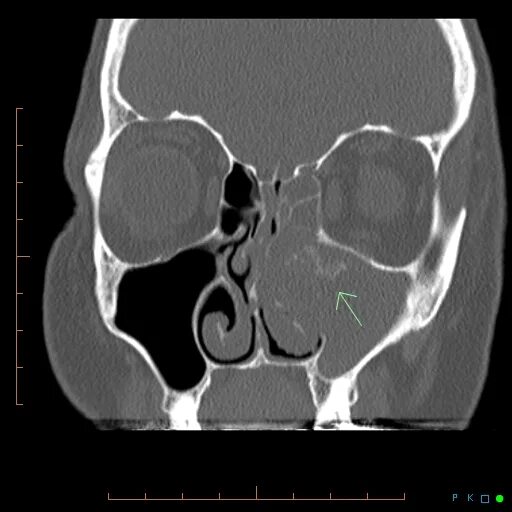

Синусит на кт